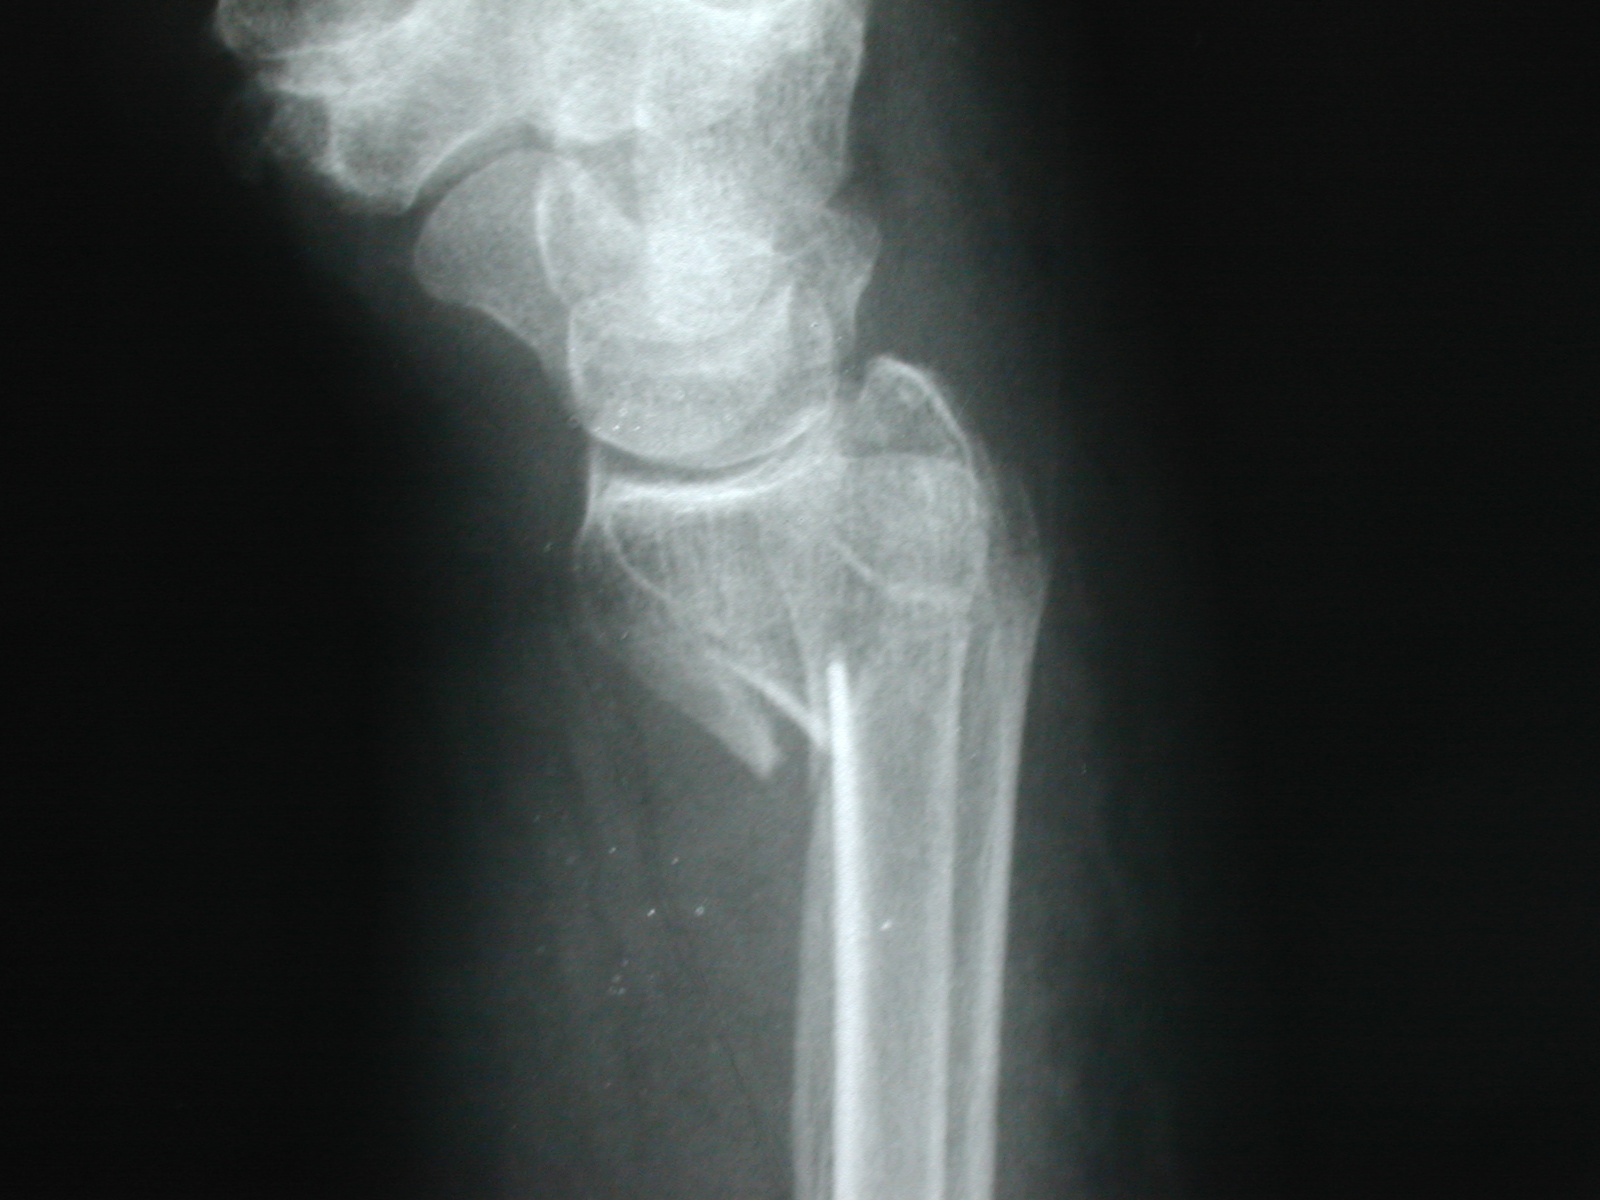

El tratamiento de una fractura de muñeca . EPIDEMIOLOGÍA: 70 %de las fracturas del antebrazo, 14% extremidad superior, 17% todas las fracturas, 1 de cada 50, Fractura . La lesión más frecuente como resultado de caídas y golpes en la muñeca es la fractura de radio distal. Estos incluyen flexión y extensión de la muñeca, rotación del antebrazo y agarre con una pelota de goma. Pérdida de la solución de continuidad normal de la porción distal del hueso radio, situada hasta 2,5 cm (4cm) de la articulación radiocarpiana y que puede o no involucrar esta articulación. Presenta diferentes .Riesgos y complicaciones de una fractura de muñeca: Suelen ser poco comunes, pero puede presentarse: Lesión de nervios y vasos sanguíneos, principalmente si presentas trastornos circulatorios o entumecimiento.La Fractura de Muñeca – Descripción y Tratamiento ¿Qué es una Fractura de Muñeca? Las fracturas de muñeca suponen el 10 % de las fracturas del cuerpo.Después de una fractura de muñeca, es posible que experimentes dolor, hinchazón, debilidad y pérdida de movilidad en la zona afectada.Fractura después de los 50: señal de alarma. Las más frecuentes son las que afectan al extremo distal del radio (llamada también Fractura de Colles ), y las que afectan al hueso escafoides. Ingresa Regístrate Contribuidores Categorías Ingresa Regístrate Contribuidor.

Descripción general. Subido por META.En general, el diagnóstico de una fractura de muñeca comprende un examen físico de la mano afectada y radiografías.Las fracturas de muñeca suelen estar causadas por: El hecho de frenar una caída poniendo la palma de la mano.La fractura de muñeca es más frecuente en las personas mayores. En este sentido, las fases de curación de una fractura de muñeca se dividen en tres etapas: la fase inflamatoria, la fase reparativa y la fase de remodelación. Una quebradura de muñeca es una fractura o fisura en uno o más huesos de la muñeca.

La mayoría de las fracturas de muñeca solo necesitan un yeso o una férula.revistaconsalud. Los profesionales sanitarios deben . El tratamiento correcto y oportuno también ayuda a minimizar cualquier complicación futura. La muñeca puede romperse o fracturarse al practicar deportes, por una caída o debido a otros accidentes.La fractura de muñeca es una lesión común y puede ocurrir en cualquier momento, causando dolor e incomodidad.Las fracturas de muñeca se clasifican según el segmento óseo afectado, los tipos de fractura de muñeca según la zona afectada son los siguientes:Fractura de Colles, es la más frecuente y se presenta en el extremo distal del radio en donde este se inclina hacia la parte dorsal de la muñeca Fractura de Smith, existe un desplazamiento del segmento . Tiempo de lectura estimado: 11 .Una fractura de muñeca es una ruptura en cualquiera de esos huesos o al final de cualquiera de los dos huesos del antebrazo.Síntomas de alarma en una fractura nasal.Imagine la escena: una persona trata de interrumpir o evitar una caída “metiendo” las manos y los brazos hacia adelante; las manos pegan contra el suelo con el peso del cuerpo y los dos huesos del antebrazo –el cúbito y el radio- se doblan o rompen justo por encima de la muñeca.Es necesario realizar ejercicios específicos para acelerar la rehabilitación de fracturas de muñeca. Normalmente, los médicos pueden identificar estas fracturas en las radiografias pero, en algunas ocasiones, se necesita una .

Según Diego Fernández la fractura de muñeca se puede clasificar en 5 tipos: Tipo I fracturas por flexión de la metáfisis; Tipo II fractura parcial, es decir, cizallamiento . Hinchazón y Moretones: Aparición de hinchazón y moretones . Sin embargo, el hecho de que se trata de una lesión muy común, no significa que su diagnóstico sea sencillo.La fractura de la muñeca es una de las más frecuentes que afectan a la extremidad superior. Fractura de Smith: la muñeca se fractu-ra cuando .La fractura de muñeca significa la pérdida de la continuidad de alguno de los huesos que la constituyen, teniendo en cuenta que la muñeca está compuesta por las regiones . Los accidentes en vehículos motorizados pueden .Las fracturas de la muñeca incluyen 1.La muñeca abierta, también conocida como fractura de muñeca, es una lesión común que puede ser causada por una caída sobre la mano extendida.0k Vistas Salud Traumatología Anatomía Apuntes de . El tipo más común de fractura de muñeca es una fractura de radio distal. La rehabilitación fractura muñeca radio puede incluir una variedad de técnicas y ejercicios.La fractura de muñeca es uno de los padecimientos más frecuentes en traumatología.? Sí, solo un apunte, pero muy necesario: hay esperanza de recuperación para todos los casos de fractura de muñeca, incluidos los que han sufrido operaciones fallidas varios meses atrás. FRACTURA DE MUÑECA META. Otras pruebas de diagnóstico por imágenes. Se produce un chasquido o un estallido en el momento de la lesión.Las fracturas de la muñeca se suelen producir por una caída sobre la mano extendida. Tiene una distribución de edad bimodal con un peak en pacientes jóvenes entre 18 y 25 años .Estas fracturas se consideran fracturas de muñeca.Tiempo de Recuperación Después de una Fractura de . Los huesos pueden ser empujados fuera de su lugar y necesitan ser fijados. ¿Cuáles son los síntomas de . Ahí es cuando se rompe el hueso largo del antebrazo (radio) cerca de la muñeca.La fractura distal de radio o fractura de Colles, es la fractura del hueso radio, el radio es el hueso más grande del antebrazo y junto al hueso cúbito son los huesos del antebrazo.La fractura de muñeca es la causa del 15-45% de las consultas en traumatología por fracturas.Aunque el entumecimiento en la muñeca puede ser causado por situaciones temporales o condiciones benignas, existen algunas señales de alarma que podrían indicar un . Por lo general, usted solo necesitará llevar una escayola, pero a veces los médicos practican una intervención quirúrgica. Las lesiones más frecuentes se producen en la muñeca cuando . La muñeca fracturada está dolorida, hinchada y sensible al tacto y, a veces, se vuelve rígida y persistentemente dolorosa. Características, riesgos y tratamiento de la fractura de escafoides.